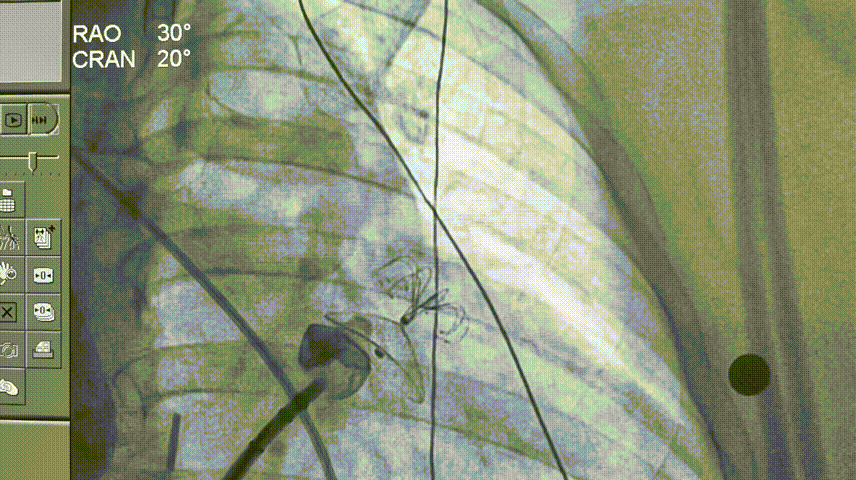

LAMax LAAC® 2430 Normal封堵器封堵盘在DSA下牵拉15s,锚定伞稳定无移位。

牵拉实验

打开封堵伞造影

符合COVER原则,将LAMax LAAC® 2430 Normal封堵器释放,再次DSA造影检查,封堵器形态无变化,封堵效果好。

释放后造影